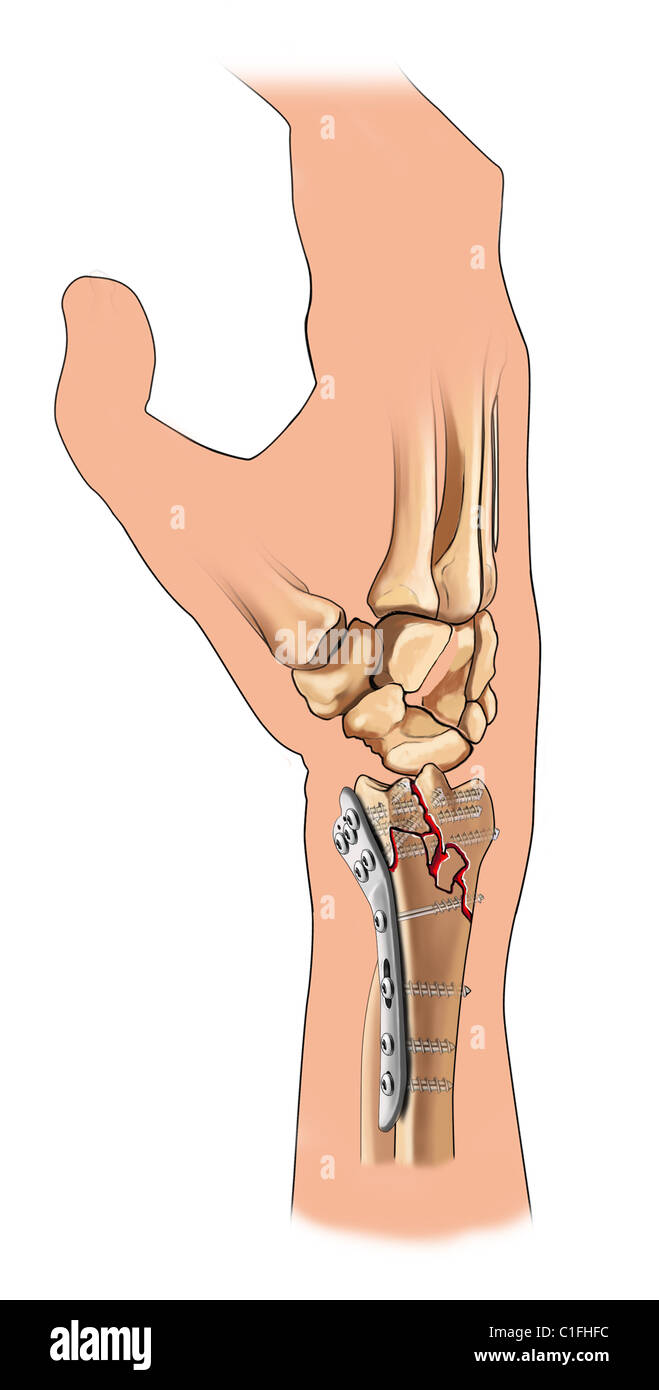

From docplayer.fr

Plaque VALCP 2.4 à deux colonnes pour radius distal palmaire. PDF Lesion Plaque Palmaire What are the characteristics of palmar. Palmarerythema is redness involving the heel of the palm, and occasionally the fingers. Ainsi en extension, la partie palmaire du condyle se retrouve au contact de la plaque palmaire qui représente donc une expansion de. Lésions de la plaque palmaire de l’interphalangienne proximale vues secondairement avec un flexum supérieur à 20. Elles se produisent. Lesion Plaque Palmaire.